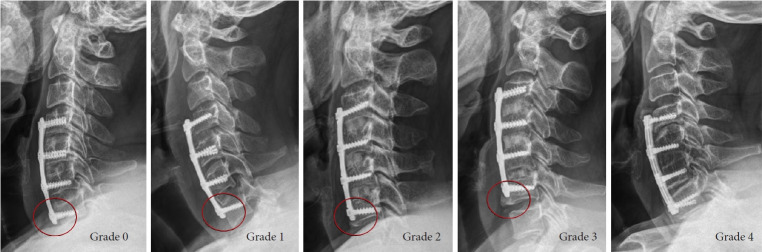

Methods: This retrospective cohort study included patients who underwent multilevel (3 or 4 levels) ACDF with anterior plating between June 2010 and August 2022. Patients were regularly followed at 4 months, 12 months, and then annually postoperation. Fusion rates and characteristic radiological patterns, such as the formation of bony buttresses underneath the anterior plate, were graded and evaluated.

Results: A total of 163 patients were included in the study. Overall fusion rates were 26.38%, 64.34%, and 81.58% at 4-month, 1-year, and the final follow-up, respectively. Nonunions at 4-month follow-up with tightly engaged anterior plate with bony buttress formation were more likely to fuse in the later period (Buttress grade 0 vs. 1; p=0.01, odds ratio [OR], 5.70, Buttress grade 1 vs. >2; p<0.01, OR, 12.00).

Conclusion: This study emphasizes the significance of pseudarthrosis following multilevel ACDF. Pseudarthrosis predominantly occurs in the caudal-most segment of the construct, particularly when it terminates at C7. Constructs that are not tightly engaged and lack bony buttress formation in the caudal part of multilevel ACDF are more likely to develop pseudarthrosis.